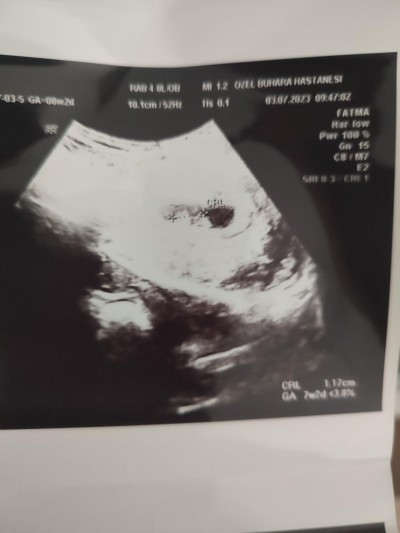

24 Temmuz 2023 Hamilelik Dönemi Genel kategorisinde (34 puan) sordu

Sizce kız mı erkek mi bazen kese şekline

göre yorum yapılıyor ondan sordum teşekkürler

Gebelik haftası 10